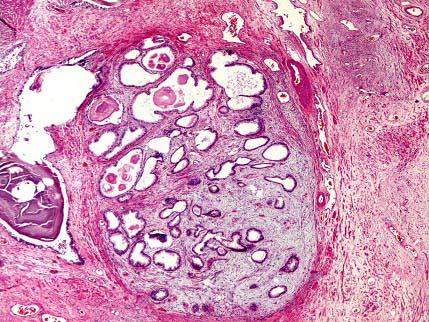

问题 男性,67岁,因前列腺肿大而行手术切除,镜检示腺体增生,间质中还出现灶状淋巴细胞浸润(如图)。你认为最有可能的诊断是 ( )

选项 A.慢性前列腺炎 B.前列腺良性增生 C.前列腺良性增生伴慢性前列腺炎 D.前列腺良性增生伴急性前列腺炎 E.肉芽肿性前列腺炎

答案 C